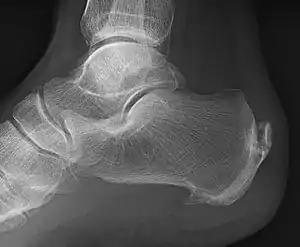

| A radiograph showing osteophytes on the posterior and inferior aspects of the calcaneus | |

When a foot is exposed to constant stress, calcium deposits build up on the bottom of the heel bone. However, repeated damage can cause these deposits to pile up on each other, causing a spur-shaped deformity, called a calcaneal (or heel) spur.[2] It is typically detected by x-ray.[3] It is a form of exostosis.

An inferior calcaneal spur is located on the inferior aspect of the calcaneus and is typically a response to plantar fasciitis over a period, but may also be associated with ankylosing spondylitis (typically in children). A posterior calcaneal spur develops on the back of the heel at the insertion of the Achilles tendon.[2]

Spur outgrowths can be detected through physical exam followed by a lateral foot x-ray.